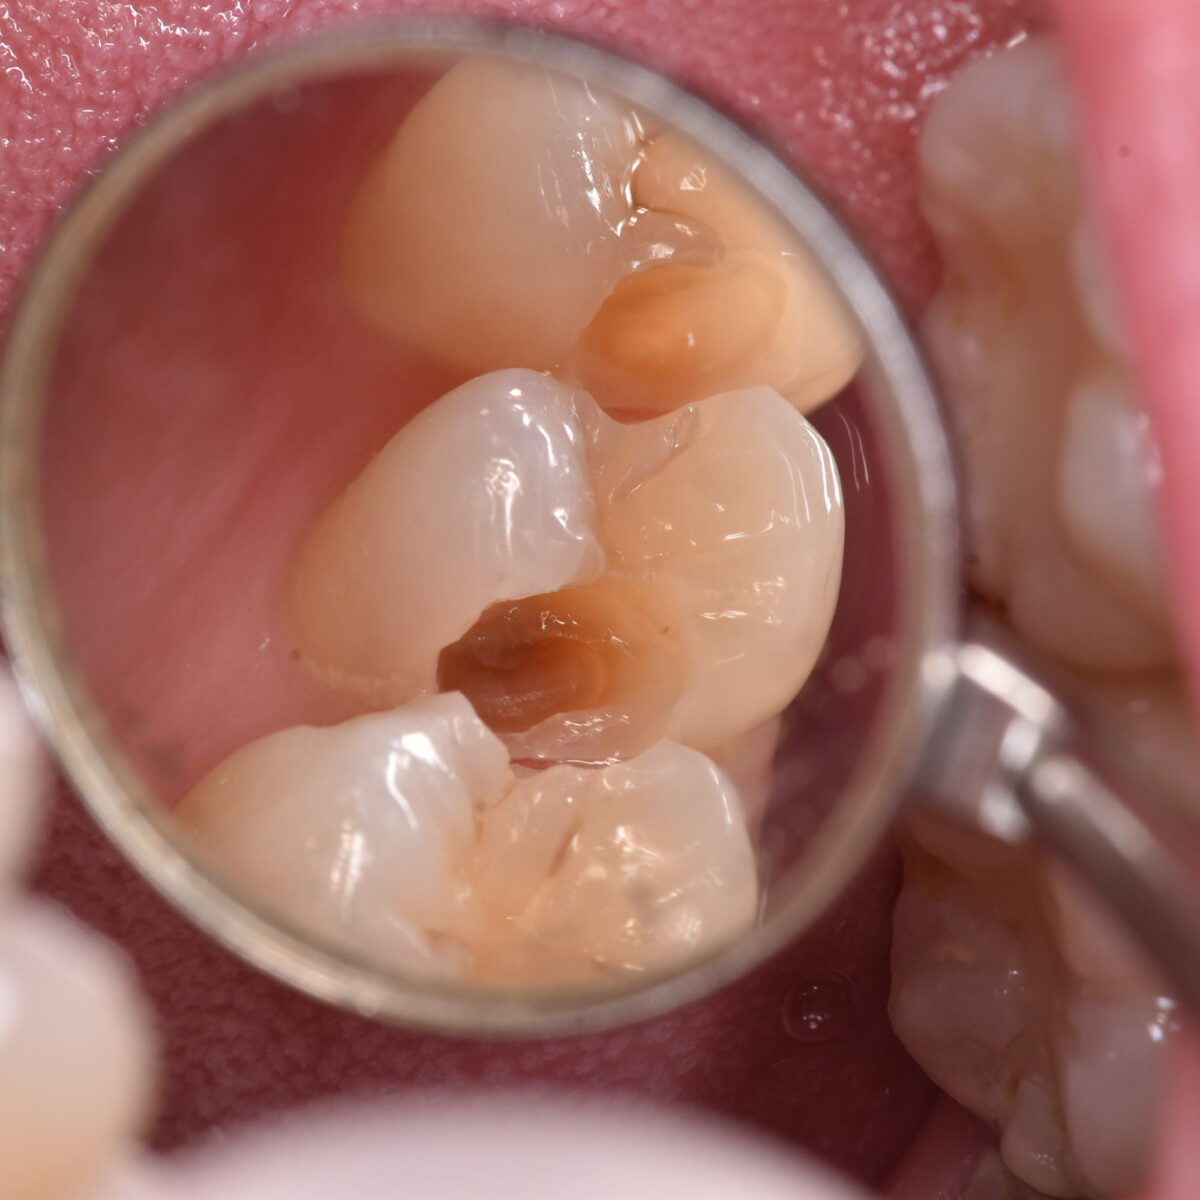

むし歯の広がりは、削ってみないとわからない。歯の神経近くまで広がっていることもある

小さなむし歯だからといって、安心できるわけではない 【東京メトロ東西線妙典駅 徒歩5分の歯医者】市川、妙典の歯科医院、めぐりデンタルクリニックの梶原です。 以前にも、似たような内容…